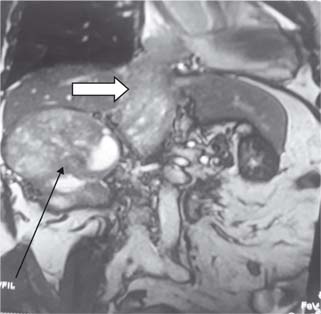

Figure 3: Level 4 thrombus with arrow (Black) showing mass in right kidney and white arrow thrombus in IVC extending to right atrium.

Figure 4: Opening of right atrium with arrow showing thrombus in situ.

Approximately, 2–16% of RCC patients had extension of tumor thrombus to RA (46). In the 2010 International Union against Cancer TNM staging system, the diameter of renal tumors and the level of tumor thrombus are important prognostic indicators. This surgical procedure has two components for the excision of renal mass and IVC tumor thrombus. In our series, majority of patients had level I thrombus (55.88%), and histopathological examination of resected specimens (19 nos.) revealed squamous cell carcinoma in 03 cases (15.78%), clear-cell carcinoma in ten cases (52.63%), papillary carcinoma in 04 cases (21.05%), and chromophobe cell carcinoma in 02 case (10.52%). In this cohort of level I thrombus, 16 patients were alive till last follow-up until 5 years with no recurrence of tumor thrombus or distant metastasis. Three patients with histopathological examination HPE of squamous cell carcinoma died within 2 years of surgery and one patient developed lung metastasis. Of the 12 patients (35.29%) with level II thrombus, 10 (83.34%) had clear-cell carcinoma and two (16.66%) had papillary carcinoma. In the level IV thrombus group (8.8%), histopathological examination revealed clear cell carcinoma with sarcomatoid variant in all three cases and only two were completely resected. In one case only biopsy was taken in view of intraoperative hemodynamic instability. All the resected specimens had a negative margin. One patient with left RCC developed solitary lung metastasis during-follow up and was put on tyrosine kinase inhibitors (TKIs) by the medical oncologist. The patient behaved well but was lost to follow-up after 3 years. The more the length of the tumor thrombus, the more challenging it is, necessitating a multidisciplinary approach that increases the complexity of the management. “Radical resection is the only curative option for RCC with a tumor thrombus in the inferior vena cava, and accurate pre operative imaging is crucial for a positive surgical outcome”. Most patients with IVC extension can be treated with nephrectomy with IVC thrombectomy without putting the patient on CPB; however, in cases of RA extension (level IV), CPB is strongly recommended (5). Digital manipulation of tumor thrombus to push it from RA into IVC without CPB can cause life-threatening blood loss. CPB offers a bloodless field and hemodynamic stability during thrombectomy from IVC and RA (2, 79). There are, however, inherent complications associated with CPB, including increase in operative time, myocardial ischemia during cross-clamp, arrhythmias, respiratory complications, and postoperative hemorrhagic drainage due to onset of coagulopathies (5, 10). In literature, some surgeons have used profound hypothermia with circulatory arrest to retrieve the tumor thrombus from RA (11, 12). The predominant limitations of this technique are its associated morbidities, including neurologic complications (delirium, psychosis, and stroke) (13, 14), thrombocytopenia, and platelet dysfunction, resulting in significant bleeding, prolonged and/or improper rewarming with postoperative hypothermia, and overall higher mortality (13, 15). Our approach in level IV thrombus (Figure 5) was beating heart on simplified CPB without cross-clamp on aorta. Beating heart is more physiological, as the heart is allowed to beat normally, maintaining a normal coronary perfusion and contractility, while offloading the heart of blood volume. As a result, this allows for smooth resumption of heart off bypass. Weaning off from CPB is quick, smooth, and easy, without having to wait for the mandatory period to replenish the myocardium with energy substrates needed in the case of an arrested heart. This reduces the operative time, and facilitates better hemodynamic stability, early extubation, and early shifting from intensive care unit to the general ward. As a result of shorter CPB time, the inherent risks of extracorporeal circulation are minimized, although not eliminated. These include less systemic inflammatory response, less coagulopathy and thrombocytopenia, thereby less postoperative bleeding and blood transfusions; less chances of embolism, stroke, and post-CPB psychosis.